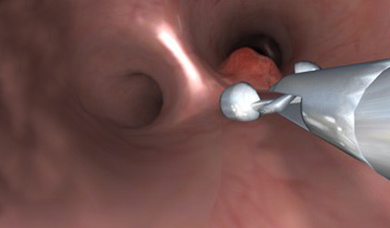

- Realistic and comprehensive bronchoscopic simulation training away from patient, designed to support both team and solo training sessions

- Complete patient management with moderate sedation dynamic complications, and reactive virtual patients

- Didactic environment enhancing the learning curve, including skill-targeted tasks, procedural tasks, aided/un-aded clinical cases – each followed by comprehensive performance feedback